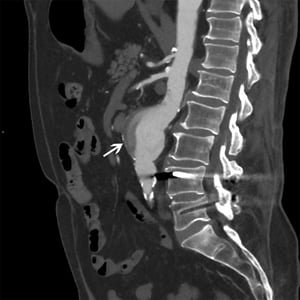

Aneurisma dell'aorta addominale (TC)

La freccia bianca mostra un aneurisma dell'aorta addominale di 5 cm con flusso eterogeneo e placca murale.

© 2017 Elliot K. Fishman, MD.